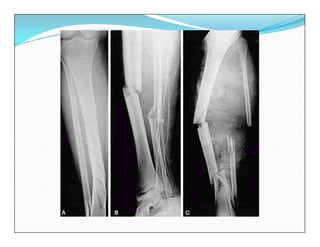

Fracturas diafisarias de la Tibia

Tratamiento Quirúrgico

 Clavo Intramedular

 Clavo Intramedular Bloqueado

Fracturas diafisarias dela Tibia Tratamiento Quirúrgico  Clavo Intramedular

Fracturas diafisarias dela Tibia Tratamiento Quirúrgico  Clavo Intramedular Bloqueado